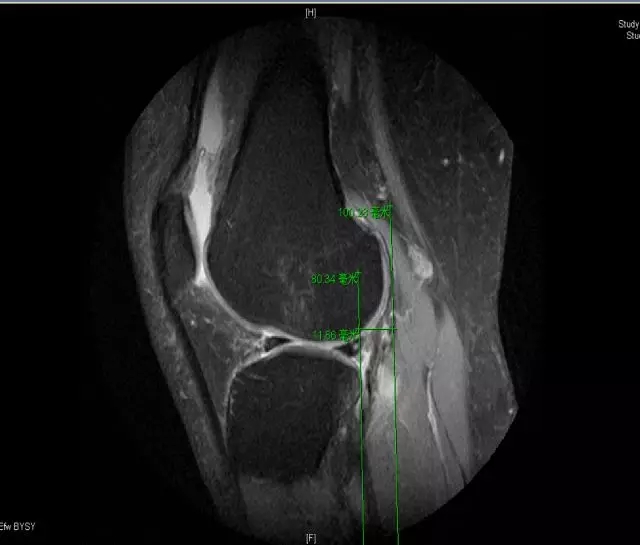

Blumensaat 角(-1.6度)

大于9-15度视为异常

前交叉韧带与胫骨平台角度(56度)

小于45-50度视为异常

后交叉韧带折弯度

弧度:0.19厘米,角度:114-123度